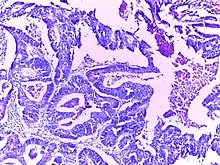

![]() | Adenocarcinoma colon | Micrograph of carcinoma colon showing malignant glands.Nuclei are small and vesicular, located at the bottom of the cell. The cells show increased nucleocytoplasmic ratio. | Category: Histopathology of colorectal adenocarcinoma | Colorectal carcinoma |